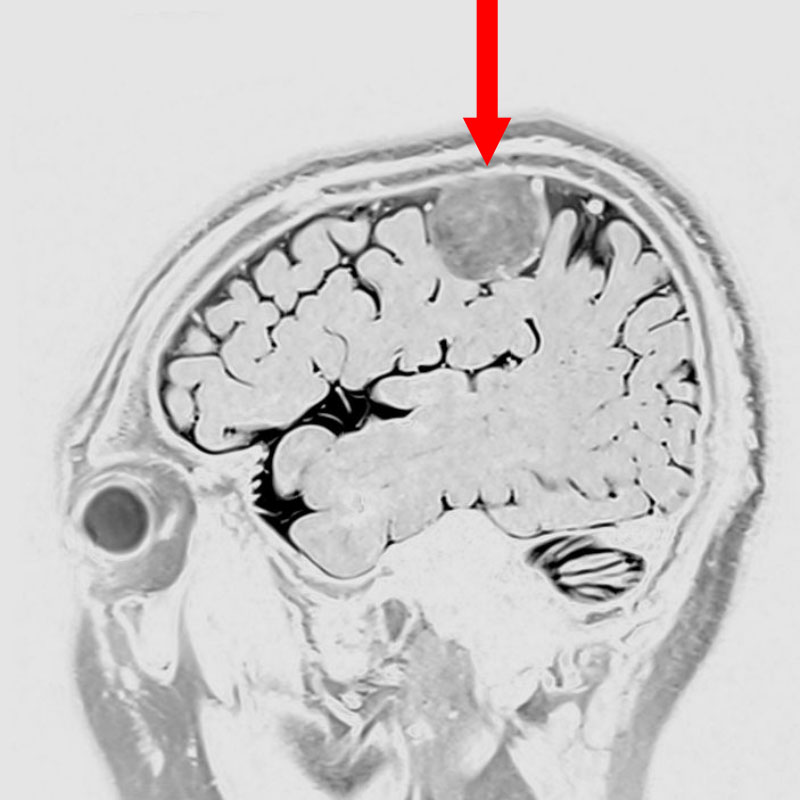

707

'25年12月

80代

髄膜腫

頭蓋内腫瘍摘出術

No.’25_109 手術前1

No.’25_109 手術前2